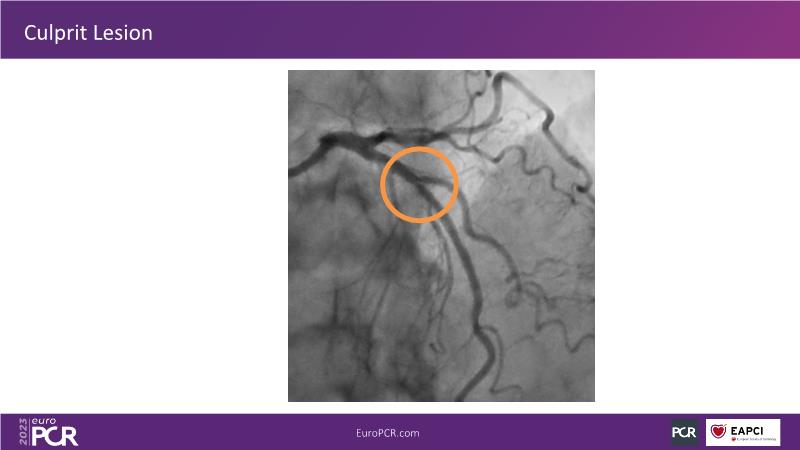

Join this session to explore the advantages of a fully optical approach in optimizing percutaneous coronary intervention (PCI) with the OptoWire III physiology wire and Nipro HF-OCT catheter. Through a practical case, you'll discover the significance of coronary physiology and intravascular imaging in bifurcation PCI and gain insights into how the performance and accuracy of the OptoWire III physiology wire can facilitate fast and reliable decision-making, particularly in side branch jailing scenarios.

- To review, through a practical case, the value of coronary physiology and intravascular imaging in bifurcation PCI